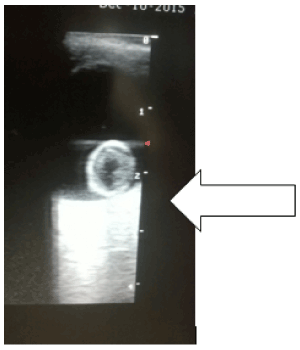

Figure 2. Coned section of an ocular echogram of the right eye of another patient. The ovoid echogenic rim lens is pendulous and obliquely orientated in the anterior vitreous [Black oblique arrow]. One pole of the lens is still attached to one of the ciliary bodies of the right eye (Partial dislocation of the lens of the right eye)